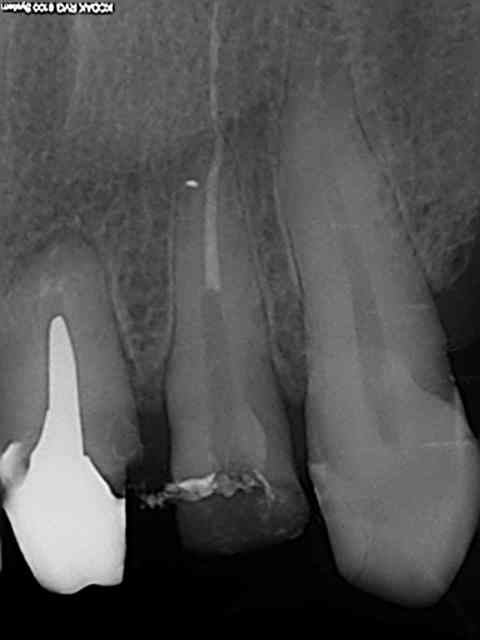

voici ma radio

qu en pensez vous ?

C'est large et assez court : Transmétal jusqu'à ce que le tenon saute. Tu fraises dans le canal si il faut. Au bout d'un moment il va venir. Tu passes les ultrasons régulièrement pour essayer de faire sauter. Mais au pire dans un cas comme ça je fraise jusqu'au bout du tenon, c'est moins dangereux que de tenter de tirer, tu ne cassera pas la dent.